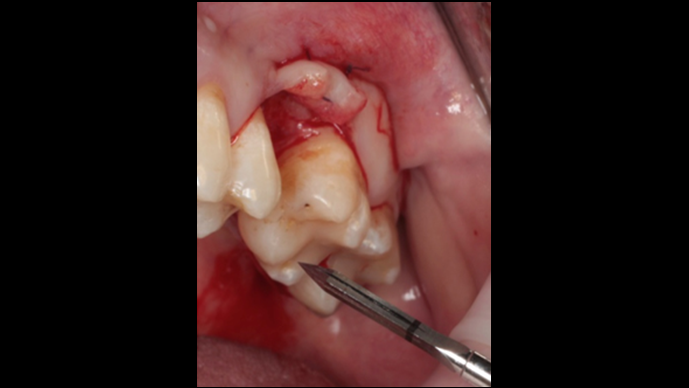

Clinical case: # 46 implant placement & GBR using i-Gen membrane for significant vertical resorption & mixed bone defect

- Courtesy of Dr. Iulian Filipov, Romania -

AnyRidge, mandibular posterior, i-Gen, resorption, bone defect, bone regeneration, space management, #46, GBR, Dr. Iulian Filipov

AnyRidge implant system, i-Gen